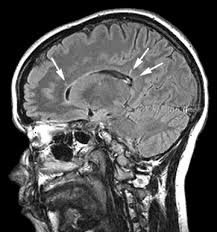

Multiple sclerosis (MS) is the most common disabling neurological disorder of young adults in Canada. In this condition, the immune system attacks the myelin sheath surrounding nerve cells. MS has traditionally been treated with injectable drugs, which are uncomfortable to use and have side effects. Only one other oral medication for MS has been approved by Health Canada and the U.S. Food and Drug Administration.

MRIs showed that patients taking 14mg of teriflunomide had a 69-per-cent reduction in the number of new abnormalities in their brains caused by MS. The reduction was 48 per cent for those on the lower dose of the drug.